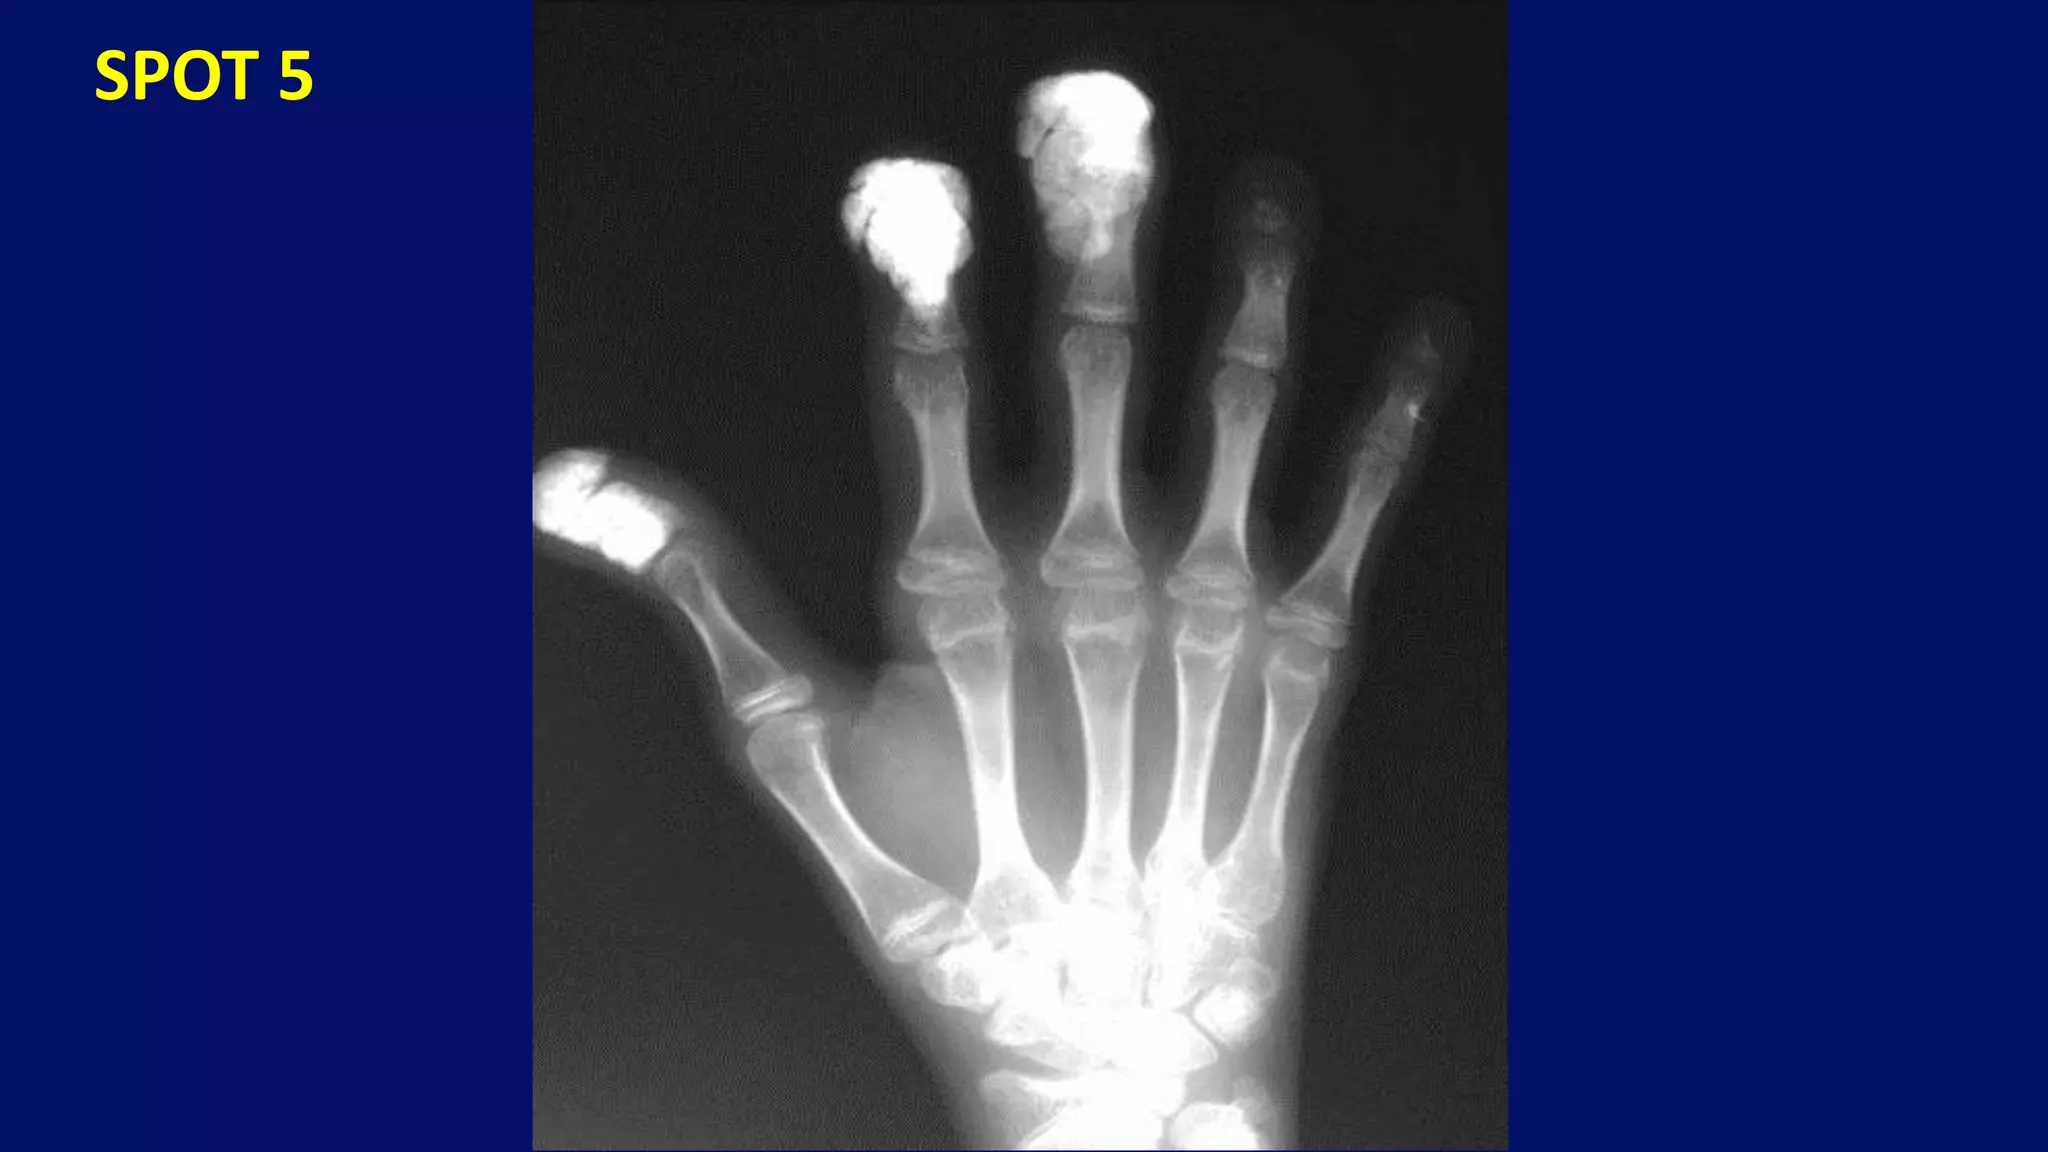

Subcutaneous calcifications alongwith destructive changes in distal IP joints

Destructive changes in the distal interphalangeal joints, as well as soft-tissue calcifications

• #81 this xray left hand shows Subcutaneous calcifications alongwith destructive changes in distal IP joints of middle, ring and little fingers.

• #136 20 years old male with hand pains and swellings. Note acrosteolysis and globular soft tissue calcifications characteristic of progressive systemic sclerosis.